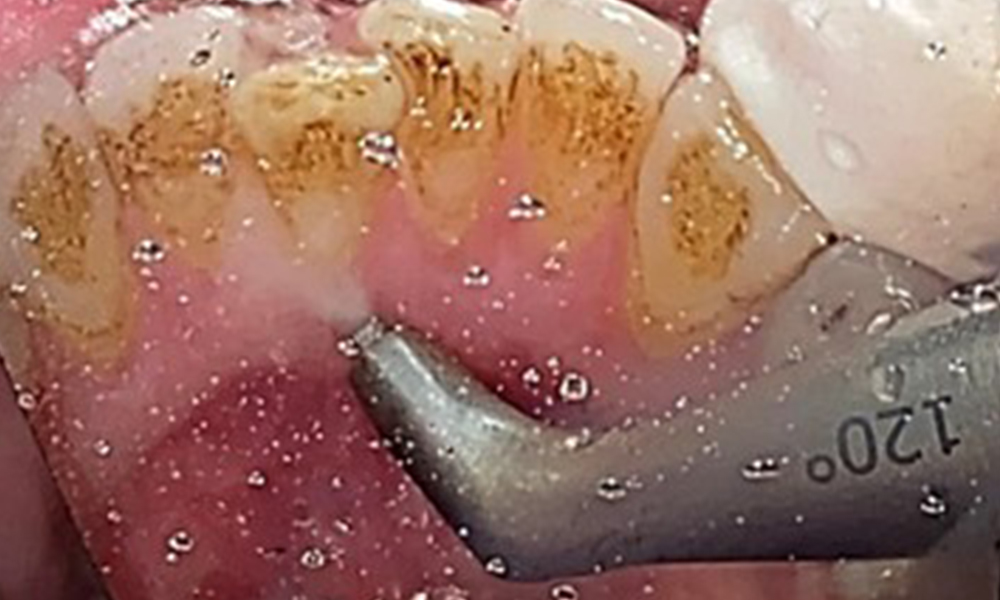

The objective would be to control disease risk by removing supragingival and subgingival biofilm. The instruments can be selected based on patient needs. First, calculus and any concretions must be removed using ultrasonic and/or manual instruments (Fig. 10).

Use of a piezo-driven ultrasonic device in the lingual area near 36 (Proxeo Ultra, W&H, shown here)

Fig. 10 Use of a piezo-driven ultrasonic device in the lingual area near 36 (Proxeo Ultra, W&H, shown here), © Dr R. Krapf